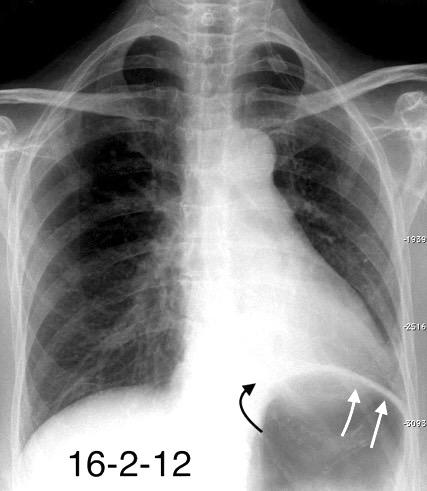

29. FALSA ELEVACIÓN DIAFRAGMÁTICA. GRASA

Grasa simulando elevación diafragmática izquierda